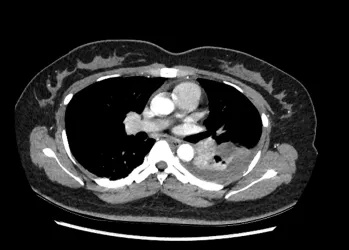

患者入院复查CTPA

患者影像检查变化

经过规范的溶栓、抗凝治疗,患者咳嗽及咳嗽时胸痛的情况明显好转,复查造影结果显示,肺梗死灶和胸腔积液均有明显改善。